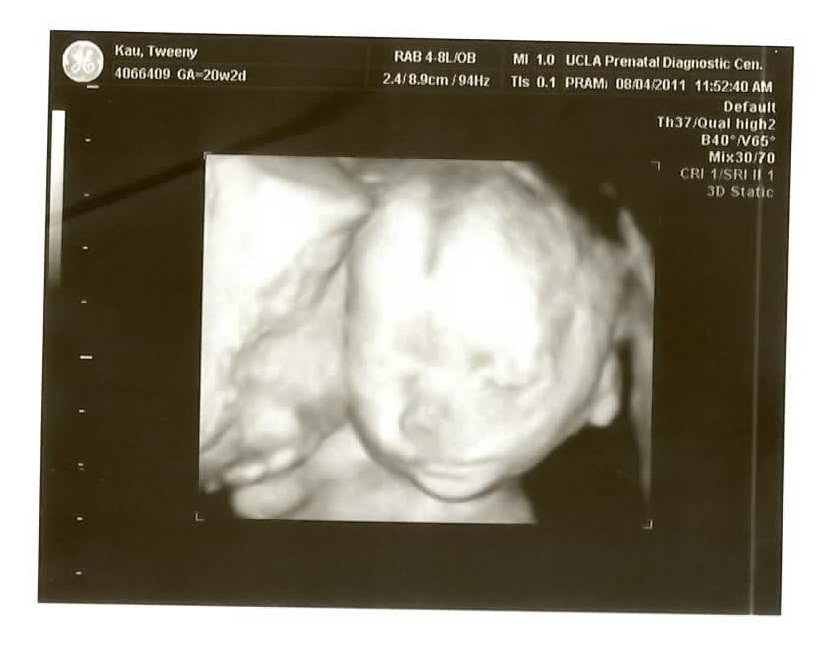

We just went back for our twenty week checkup/ultrasound and as usual they gave us a DVD which I have ripped to YouTube (it’s just everything they did.. 17:10 long.. I cut out the first 2:20 of the intern bumbling around to keep it under the 15 minute YouTube maximum).

See if you can figure out what gender it is from the ultrasound pics! Check the comments for the answer!

The 3D pictures are kind of funny because the ultrasound technicians are all like “So CUTE!” and all I can think is “for a pig face!” The one face-on isn’t so bad if you don’t look above the bottom lip I guess..